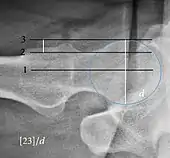

Measurements of impingement on X-ray.[notes 1][20]

MeasurementImageTargetNormal value

Center-edge angle of Wiberg

The superior-lateral coverage of the femoral head.

• >20° (<55 years old)[notes 2]

• <24° (>55 years old)[notes 2]

• >40° indicates overcoverage

Crossing ratio Percentage of acetabular walls crossing. Normal acetabulum is oriented in anteversion. Its value ranges from 15 to 20° in the equatorial plane of the acetabulum and decreases gradually towards the acetabular roof, where normal values range from 0 to 5°. Retroversion of the upper part of the acetabulum has been related with pincer type impingement. In radiography the presence of a "crossover sign" is produced when the posterior wall of the acetabulum crosses the anterior wall before reaching the acetabular roof. It is a sign of acetabular retroversion and it has been linked with overcoverage and pincer impingement. Nevertheless, this sign has been described in 6% of the normal population. Therefore, more important than its presence is the percentage of crossing. <20%

• Higher is significant crossing

Femoral head-neck offset

Measured in cross-lateral view.

Offset of the femoral head with regard to most prominent aspect of the femora neck>10 mm

Offset percentage Femoral head-neck offset related to femoral head diameter >0.18

• less indicates high risk of cam type impingement

Tönnis angle Slope of the sourcil (the sclerotic weight-bearing portion of the acetabulum) 0 to 10°

• >10° is a risk factor for instability

• <0° is a risk factor for pincer impingement

Caput-sourcil angle[21] Superior to the Tönnis angle in cases without joint space narrowing or subluxation.[21] The medial point of the sourcil is at the same height as the most superior point of caput femoris. −6 to 12°[21]

• >12° is a risk factor for instability

• <-6° is a risk factor for pincer impingement